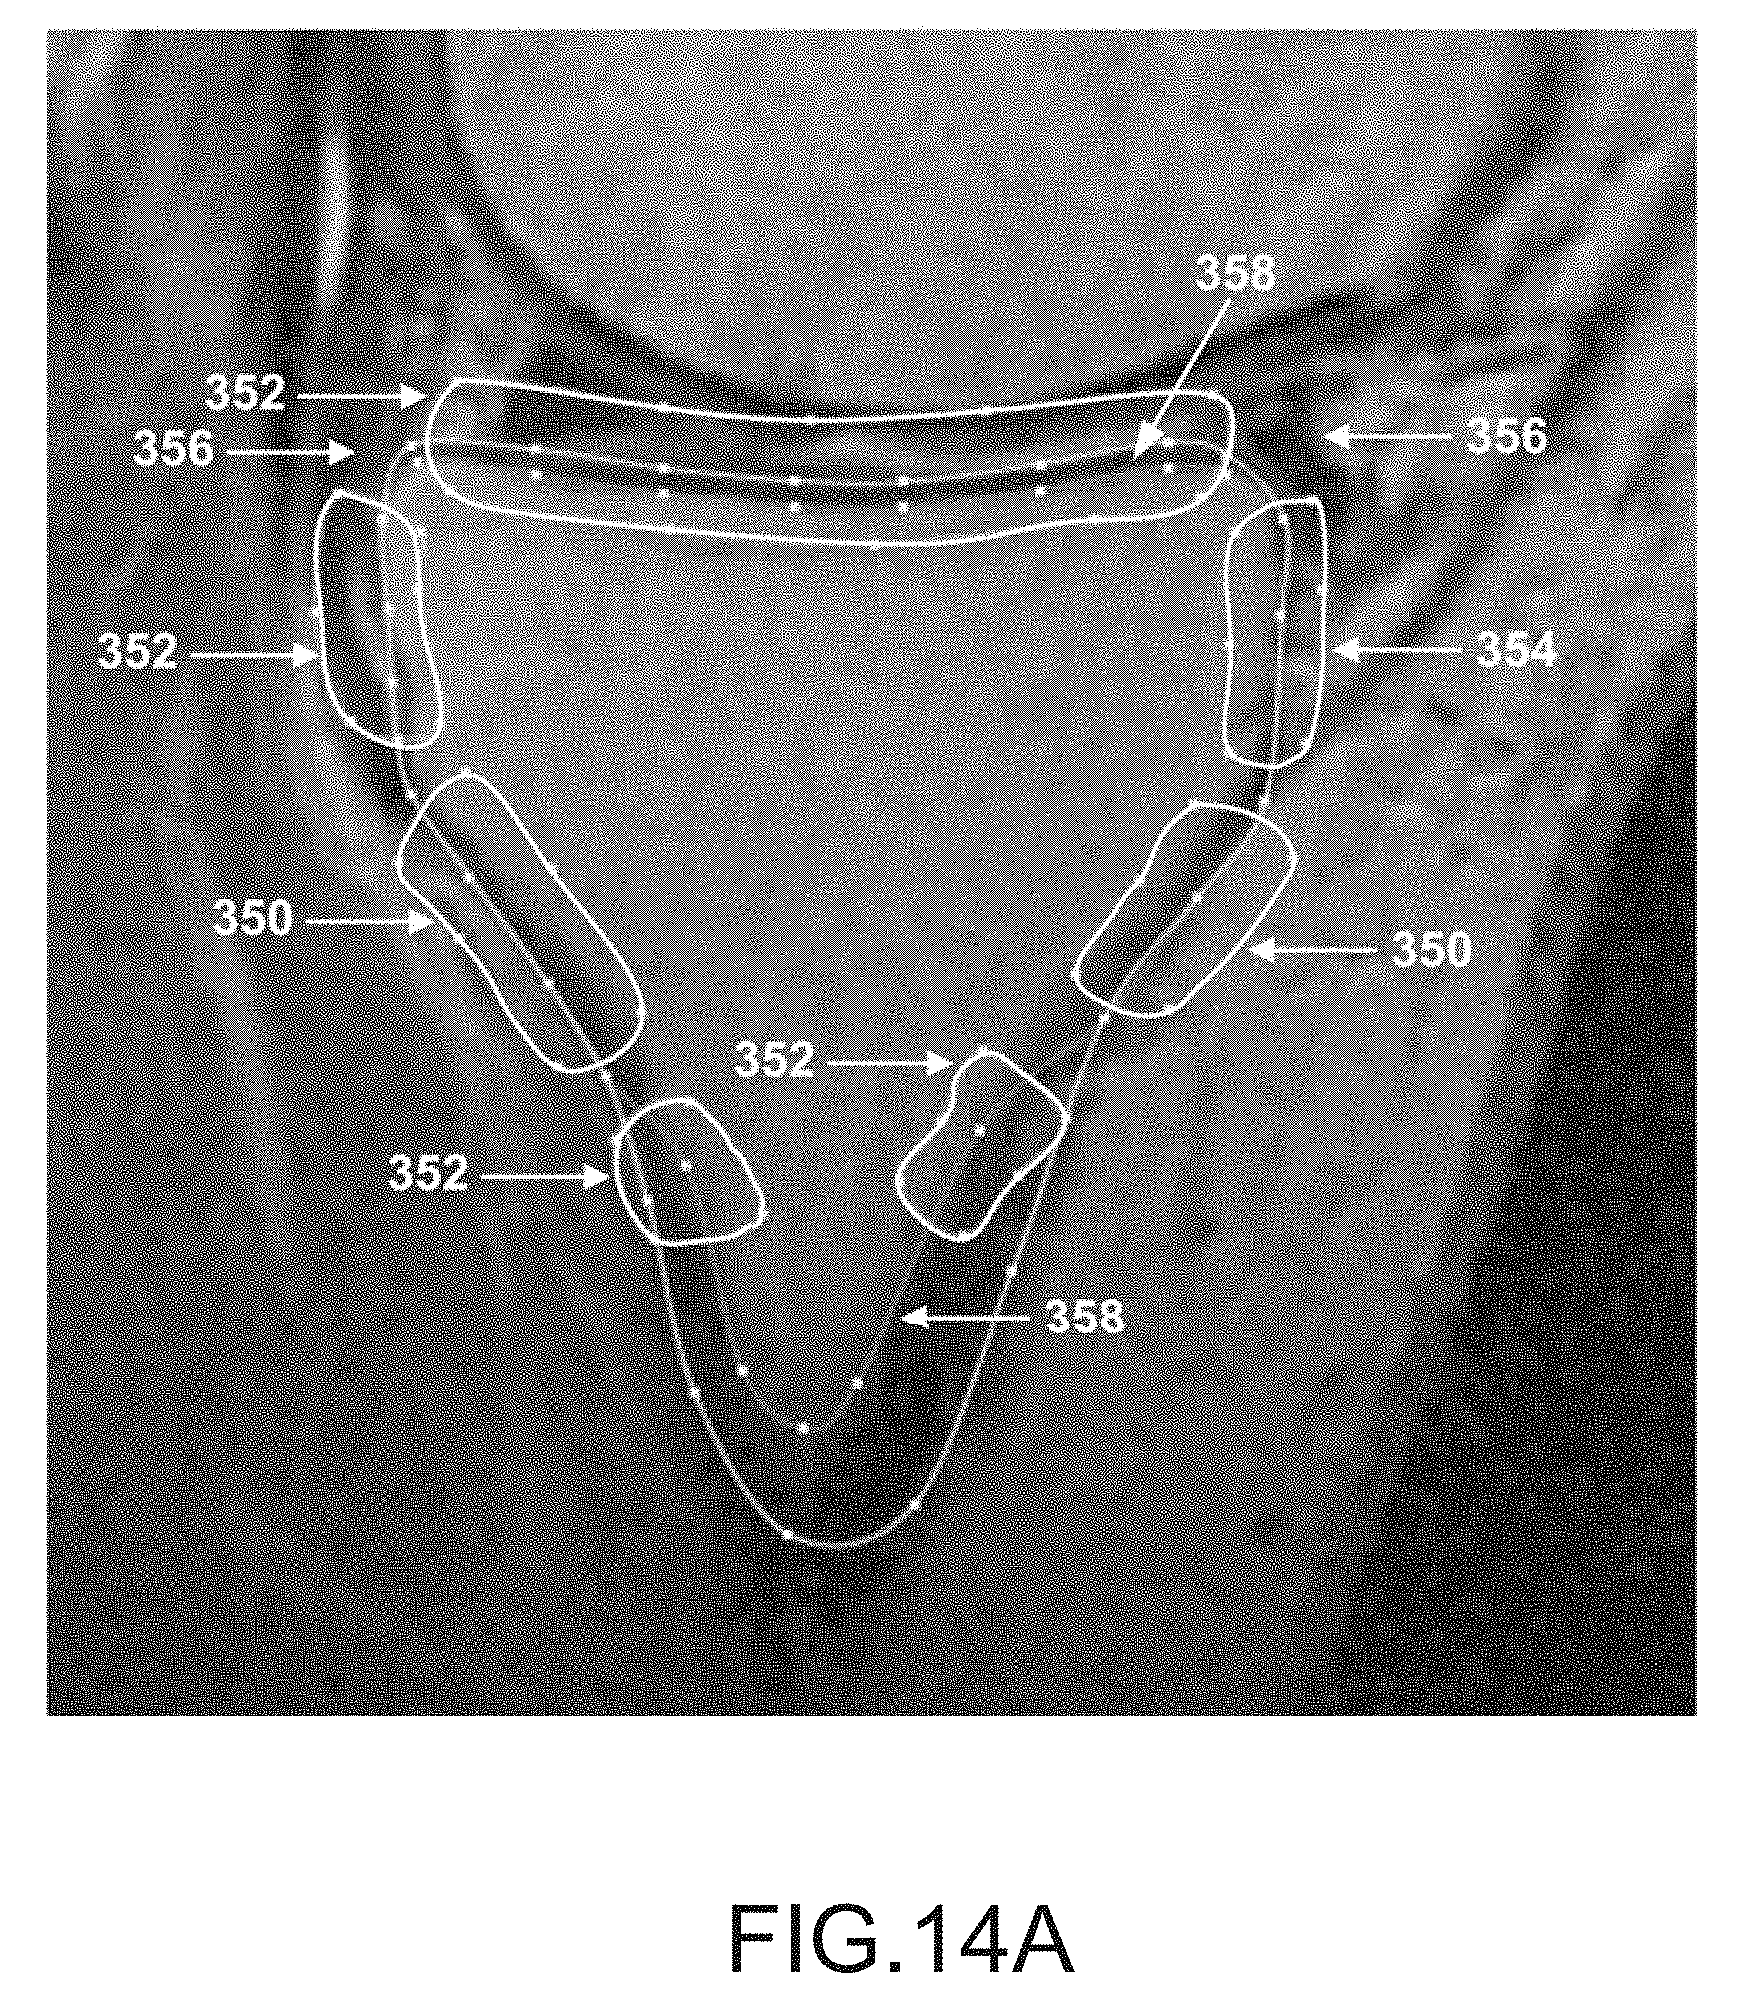

FIG. 14A is a sagittal plane image slice depicting anchor segmentation regions of a tibia.

[0070]

FIG. 14B is a sagittal plane image slice depicting anchor segmentation regions of a femur.